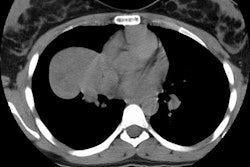

in the thymus; when they do, they are aggressive tumors that affect adults who

usually present with chest pain, cough, and dyspnea. Thymic carcinoids manifest

radiologically as anterior mediastinal masses and may mimic thymomas. Thoracic